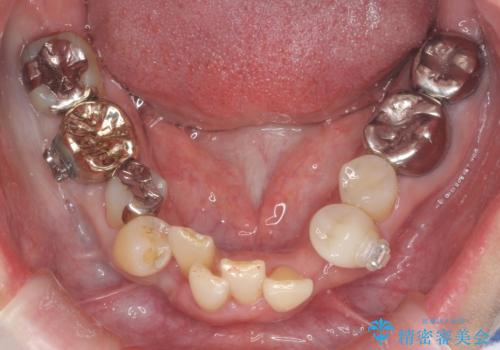

50代女性 八重歯を矯正治療 歯並びの中等度のがたつき

- ワイヤー矯正

- 八重歯の矯正を希望されて来院。

歯は入りきらないため、通常の抜歯矯正を行いました。

歯がご年齢的に動きにくいため、被せ物のやり替えを含めて治療期間の短縮を図りました。

矯正治療自体は2年半、虫歯治療等で1年ほどかかっています。

詰め物や被せ物のやり替えも併せて行っているため、治療期間を比較的短縮できました。